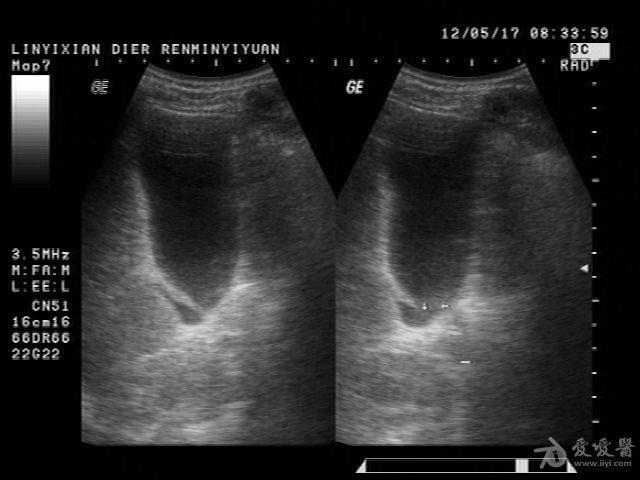

患者男性,57岁,十多年前曾患“肝炎”,近一年在它院曾诊断为:肝硬化。一月前在市医院治疗发现有腹水形成并发现有“腔梗”。古来我院就诊。B超提示:肝脏病理声像(肝光点增粗、肝硬化声像)胆囊图像如图。腹盆腔未及游离暗区回声。

这个胆囊颈部的暗区可以称“胆囊憩室”吗?

邹褶吧,不是憩室

很明显的胆囊皱褶,这种现象应该很常见的,肝硬化的时候胆囊比正常要大些

应该是胆囊皱褶。